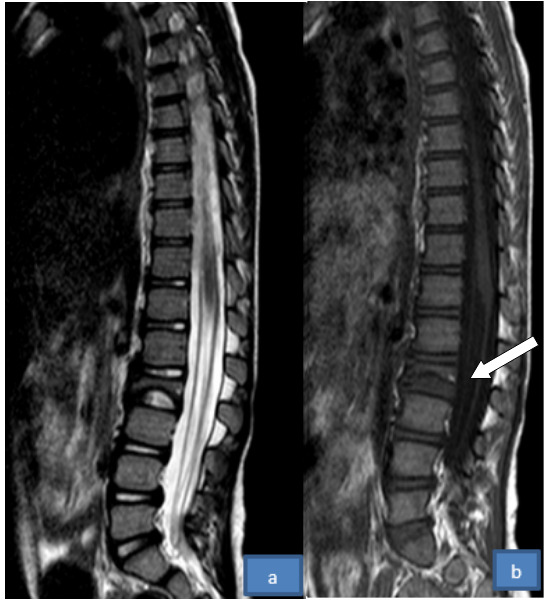

At the age of 4 years and 3 months, she came back with a complaint of left eye swelling. A computed Tomography (CT) scan showed a left eye globe soft tissue mass suggestive of Retinoblastoma and was treated with External Beam radiotherapy for 3 weeks. A year into her follow up she came with an acute lower back pain radiating down to her thighs bilaterally, neck swelling, and difficulty walking. Neck and Abdominal Ultrasound showed bilateral cervical, mesenteric and para-aortic lymphadenopathy. Bone marrow biopsy was taken which demonstrated normal trilineage hematopoiesis, and Thoraco-Lumbar spinal MRI was suggestive of vertebral metastasis evidenced by L2 vertebral collapse (Fig 4). In light of the new diagnosis of vertebral and Lymph node metastasis, she was treated with high-dose intravenous dexamethasone, and 6 cycles of combination chemo-radio therapy including vincristine, doxorubicin, cyclophosphamid, and MESNA. The patient had no residual complications from the vertebral metastasis, and systemic studies didn’t show involvement of other body parts.

_and_t1_(b)_lumbar_mri_showing_vertebral_body_height_loss_of_l2_(white_arrow).png)